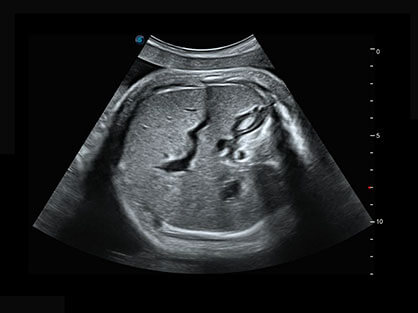

• 产科自动测量

自动获取标准切面,自动完成测量,帮助医生快速完成检查,同时提升测量准确性。